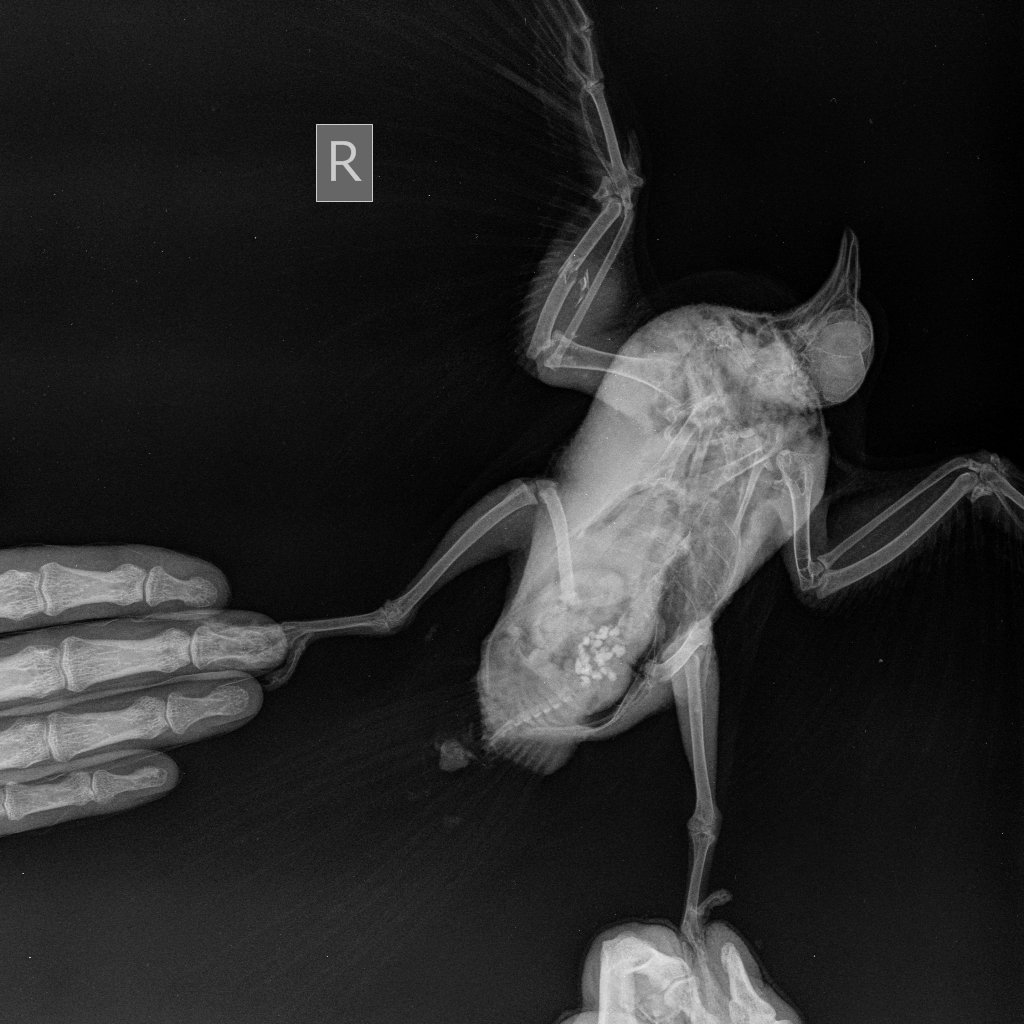

Zosia Опубликовано 29 июля, 2021 #15 Опубликовано 29 июля, 2021 Вам надо сделать еще раз снимок, с аккуратно и полностью раскрытым поврежденным крылом. Фиксировать к основанию (над кассетой) бумажным скотчем, придерживать крыло у плеча. Потому что на вашем первом снимке- полный многооскольчатый перелом локтевой кости с малым смещением, а вот лучевая кость выглядить выбитой (оторванной), что озанчает внутрисуставный перелом...Но т.к. крыло снято не в раскрытом состоянии- степень повреждения оценить трудно. Что там с легкими- а что-то есть- так же плохо видно. С успехом это м.б. микоплазмоз, или клебсиелльная пневмония, или тупо аллергическая реакция на что-то. Глубокий мазок из глотки и помет- и красить по Циль-Нильсену. Смотреть КУМ и криптоспоридии. Ну и банальный общий анализ помета (копрограмма) Пока основная терапия- снятие боли (НПВС), травматин, миорелаксант можно (толперизон). Фиксация - магкая, в сетчатый трубчатый бинт, со свободным здоровым крылом. Вот аткого типа: https://public.fotki.com/Shemlik/bae5/b70c.html https://public.fotki.com/Shemlik/bae5/2.html#media https://public.fotki.com/Shemlik/bae5/3.html#media

Cara Mia Опубликовано 4 августа, 2021 Автор #17 Опубликовано 4 августа, 2021 Добрый день! Снимки нового рентгена голубя были сделаны в клинике "Главное Хвост". Лечащий врач этой клинике после осмотра и на основании этих снимков сделала такую выписку (фото) с диагнозом (диф.) Аэросаккулит, (диф.) Аэроцистит. По перелому сказала, что оба крыла работают, оно начинает срастаться, но необходимо извлечь остатки раздробленной кости, для чего нужна операция, а вывихи вправлять в Беларуси не могут. Посоветовала записаться на прием к главному врачу-орнитологу клиники А. Полозу, который до 14.08. находится в отпуске. Назначены следующие препараты: 1. Амоксициллин 250 мг - внутрь по 1/16 содержимого капсулы 1 раз в день, на протяжении 10 дней. 2. Мелоксидил сусп. - внутрь по 0,1 мл 1 раз в день, на протяжении 10 дней. 3. Нистатин 500000 ед. - внутрь по 1\6 таблетке 2 раза в день, на протяжении 14 дней. 4. Карсил - внутрь по 1/10 таблетки 1 раз в день на протяжении 14 дней. Не входит ли это в противоречие с уже существующим назначением другого врача?: 1. Ципрофлоксацин, 250 мг, внутрь по 1/10 таблетки 2 раза в день 3 недели (ПРОДОЛЖЕН С 14 ДО 21 ДНЯ ПОСЛЕ ПЕРВЫХ СНИМКОВ РЕНТГЕНА) Курс начат 22.07 Курс будет закончен 12.08 2. Мелоксикам 7.5 мг, внутрь по 1/10 таблетки 1-2 раз в день, 7 дней, далее по состоянию Курс начат 20.07 Курс закончен 27.07 3. Метронидазол 250 мг внутрь по 1/8 таблетки 1 раз в день 5-7 дней Курс начат 20.07 Курс закончен 26.07 4. Нистатин 500000 ед. внутрь по 1/4 таблетки 2 раза в день в течение месяца (ДОБАВЛЕН ПОСЛЕ ПЕРВЫХ СНИМКОВ РЕНТГЕНА) Курс начат 22.07 Курс будет закончен 22.08 5. Празицид, суспензия для котят внутрь по 0.3 мл 2 раза с интервалом 14 дней Курс начат 23.07 Курс будет закончен 07.08 6. Стронгхолд 1/2 пипетки 2 раза с интервалом 21 день Курс начат 18.07 Курс будет закончен 07.08 СОСТОЯНИЕ: Голубь стал беспокойным, постоянно пытается выбраться из контейнера, часто машет крыльями. Ест хорошо, по назначению врача (каши, семена подсолнечника, льна), морковь и салат добавляю,но он не ест почти). Несколько дней назад цвет стула изменился на зеленый (фото), врач связала это с большим количеством медпрепаратов. Во время кормления лекарствами через пипетку сейчас вертит головой, оказывает сопротивление (раньше такого не было). Также при приближении руки убегает, вырывается и немного "кряхтит" (так, как это делают утки). Звук могу скинуть, если нужно. На приложенных гифках он сегодня после приема у врача, в состоянии стресса. Также Ахова птушак Бацькаўшчыны (@apb_birdlife_belarus посоветовала мне связаться с Зоей Кенько. Спасибо ей большое, что она сразу же ответила, и помогла с расшифровкой назначений, а также с контактами хороших хирургов и терапевта для проведения операции. АНАЛИЗЫ: На анализы есть возможность записаться в субботу, этого врача советуют консультант Зоя Кенько и Валерия Сороко (ВетТаргет). Стоит ли ждать продолжать курс, менять курс лечения, не дожидаясь анализов (мазок из зоба, копрограмма) до субботы хорошего врача (Вересовая Екатерина)? К сожалению, в других клиниках или не делают эти анализы, или (по отзывам волонтеров и хозяевов) делают их не совсем качественно. Прошу Вас помочь с диагностикой голубка и спасибо большое за помощь! @Zosia @OFA @маленький принц

Zosia Опубликовано 8 августа, 2021 #21 Опубликовано 8 августа, 2021 Срастаются. Будет некоторое ограниечение в функционале, но рабочее. А отломок- может и сам отторгнуться, через образовавшийся (в идеале) свищ. Остеогенон проперйте. 1/20 капсулы в сутки, три недели.